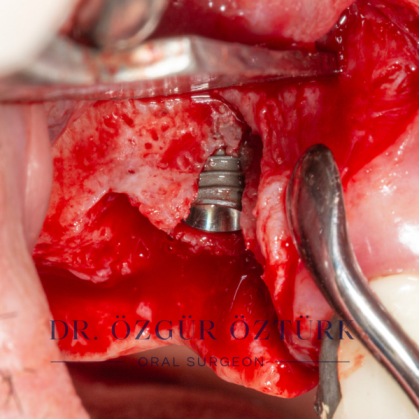

İmplant etrafındaki kemik açıklığını kemik grefti ile tedavi ettiğimiz vakamız